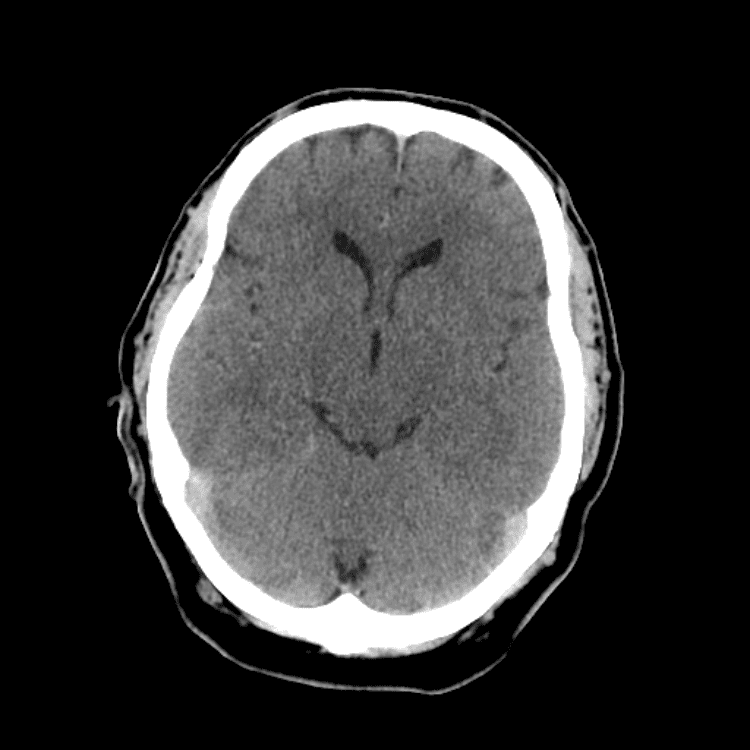

Nontraumatic Brain

Practice

Simulates call by including subtle or difficult cases and some normals.